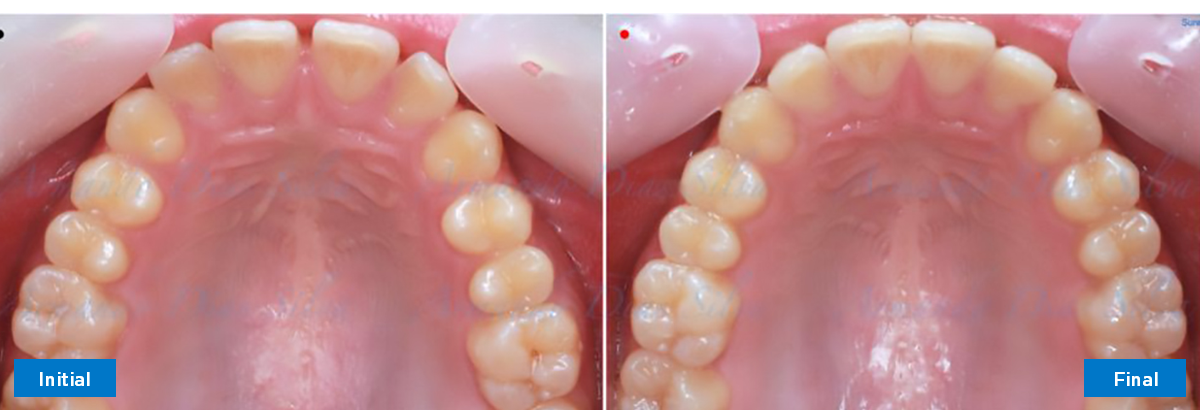

• Espaciamiento leve de las arcadas superior e inferior (deficiencia transversal de 3,45 mm)

• El primer molar superior derecho está en una posición más mesial que el primer molar superior izquierdo

• Deficiencia transversal maxilar leve (3,45 mm)

• Desrotar y distalizar los molares superiores

• Sin expansión maxilar, respetando la envoltura periodontal